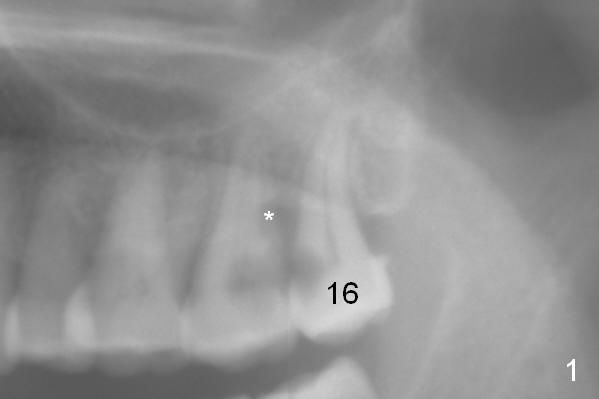

Once an implant is placed at the site of #15, the tooth #16 is extracted (Fig.4). With a piece of gauze in the implant well, allograft/Osteogen is placed around the implant (Fig.5 red circle), while collagen plug in the socket of #16 (Fig.5 brown) if necessary. After removal of the gauze from the implant well, an abutment is placed (Fig.5 pink). More graft is placed around the implant shoulder (Fig.6 white circles). An immediate provisional at #15 could be extended distally to cover the #16 socket (Fig.7 yellow). Two weeks later the provisional is modified (Fig.7 grey dashed line) to remove the distal extension.